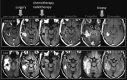

Fig 4.

Pseudoresponse is characterized by a marked decreased in the enhancing portion of the lesion some months after initiation of treatment. However, in some such cases, the FLAIR sequence shows a clear expansion of the lesion.

Fig 5.

Pseudoresponse. A 47-year-old man with GBM. A reduction of the enhancing portion of the lesion is observed 1 day after initiation of cediranib treatment. Four weeks later, besides a continuing reduction in the enhancing portion, an expansion is observed in the FLAIR images. Expansions in both the enhancing area and abnormal hyperintense areas consistent with tumor progression were observed subsequently.